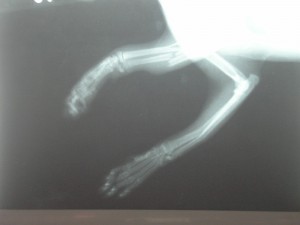

Sisi byla nalezena 29.03.2006 na sídlišti s polámanými předními

packami. Utrpěla

fraktury obou předních končetin, z nichž jedna byla tříštivá fraktura loketní

a vřetenní kosti, došlo také ke zdevastování měkké tkáně.